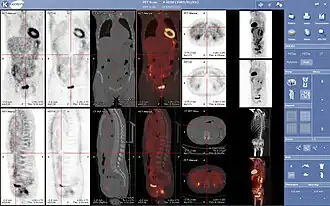

- 3D: ОФЭКТ — это трехмерный томографический метод, который использует данные гамма-камеры из многих проекций и может быть реконструирован в разных плоскостях. ПЭТ использует обнаружение совпадений для отображения функциональных процессов.

ОФЭКТ-сканирование печени ядерной медицины с мечеными технецием-99m аутологичными эритроцитами. Очаг высокого поглощения (стрелка) в печени соответствует гемангиоме.

Проекция максимальной интенсивности (MIP) позитронно-эмиссионной томографии (ПЭТ) всего тела у женщины весом 79 кг после внутривенной инъекции 371 МБк 18F-FDG (за один час до измерения).

- Гибридные методы сканирования

Нормальная ПЭТ/КТ всего тела с ФДГ-18. ПЭТ/КТ всего тела обычно используется для выявления, определения стадии и последующего наблюдения за различными видами рака.

Аномальная ПЭТ/КТ всего тела с множественными метастазами рака. ПЭТ/КТ всего тела стала важным инструментом в оценке рака.